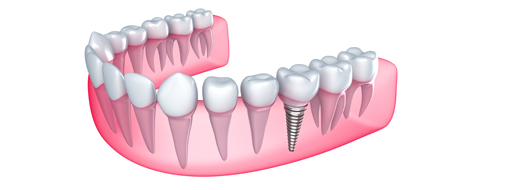

Implantología Oral

Tratamiento de Implantología Oral

Este tratamiento reemplaza las piezas dentarias faltantes con pernos de titanio anclados al hueso, los que posteriormente son rehabilitados mediante coronas de metal porcelana, ofreciendo una apariencia natural de la pieza artificial.

En Prisma Dental te ofrecemos una solución para la pérdida de piezas dentales de manera definitiva. Con la implantología oral no tendrás que volver a preocuparte por la pieza perdida.